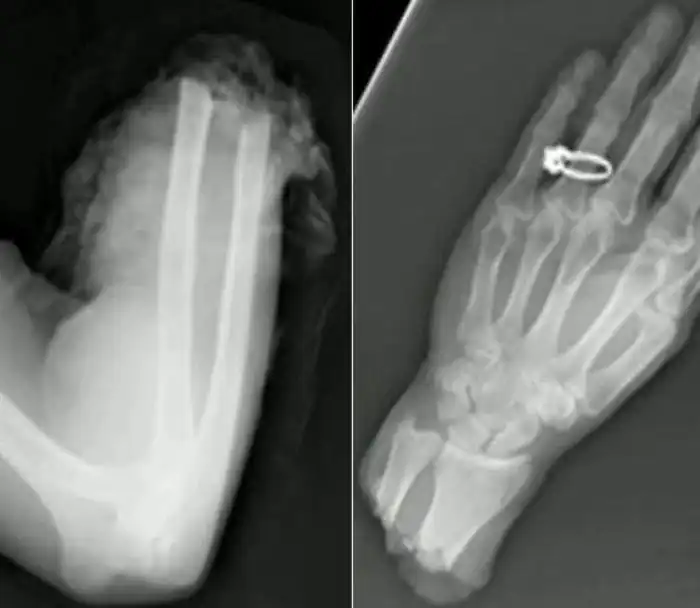

Необычные предметы в теле людей на рентгеновских снимках

На рентгеновских снимках людей порой можно обнаружить самые необычные предметы, которые находятся в их теле.